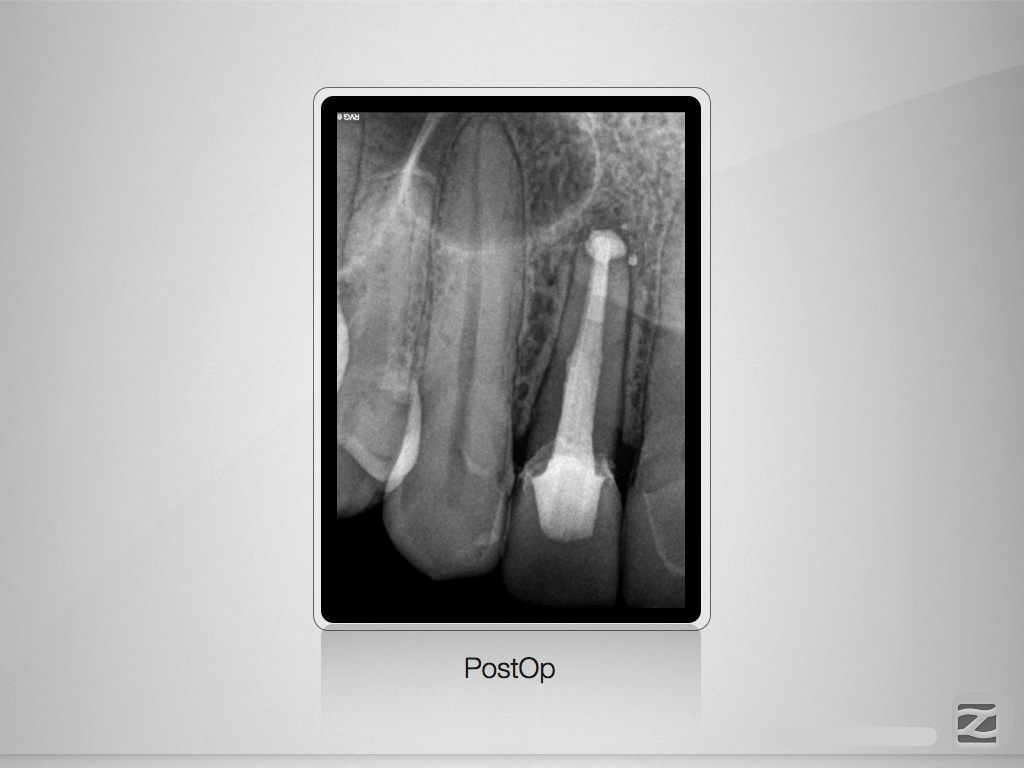

Der Schein trügt